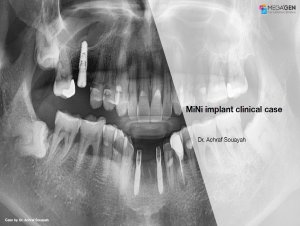

e.g. product name, treatment solution, author, clinician name